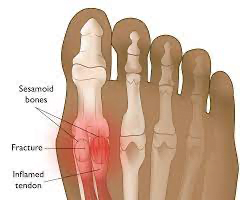

Sesamoiditis

• Typically, first toe

• A foot with bones and bones highlightedDescription automatically generated with medium confidence